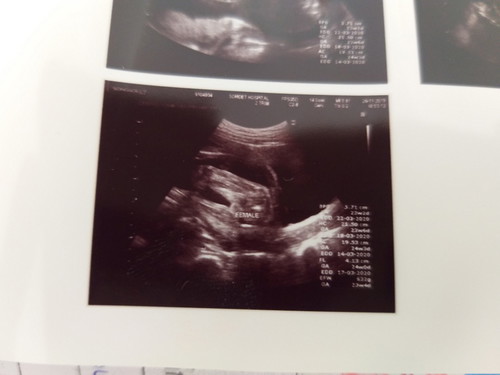

สาวน้อยของแม่ 24w

เพศหญิงแบบนี้ชัดเจนใช่มั้ย กลัวพ่อผิดหวัง เพราะคุณพ่ออยากได้ผู้หญิงมาก

น่าจะชัวแล้วนะคะแม่ ไม่เห็นมีอะไรยื่นออกมา เชื่อแบบที่เห็นไว้ก่อนค่ะ แต่ก็มีบางคนซาวเพศผิดพลาดยันคลอด แต่ก็น้อยมาก คงไม่เกิดกับเราหรอก แต่ถ้าจะเกิดก็ช่างมันเถอะค่ะ 😆